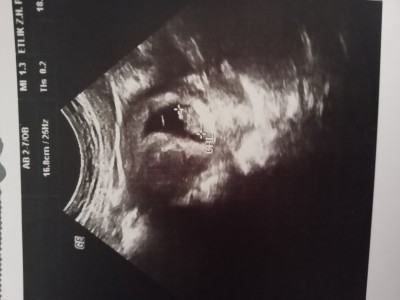

Kesem böyle kanama yok gayet normal sadece bel agrım var sorun olur mu düzelir mi doktorda iyi yada kötü bişey söylemedi küçük kalp atışlarında duymuştum.

Gebelik haftası 6+6

Önemsemeyip dikkate almadımı bilgi vermedi mi acaba diye düşünüyorum herkesin yuvarlak top gibi kesesi var benimki Bi ilginç geldi bana bebito iyidir inşallah

İlk haftalar benim keseninde sekli bi degisikti. Sonra düzeldi. İlk haftalarda normaldir sanırım doktorunuz bir sey demediyse korkmayın. Felaket tellalı bitmez burda siz doktorunuzu dinleyin :)

image8 haftalıkdı benimde burda canim simdi kocam oldu korkma sadece suyu bol ic demisti bana duzelmesi icin